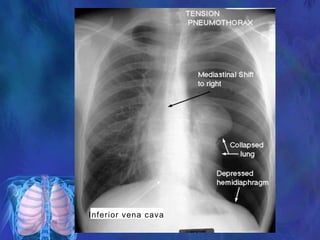

Air enters pleural space and becomes trapped leads to

pressure increase

Increased pressure which collapses lung and shifts

mediastinum to unaffected side

Increased dyspnoea and compressed heart and great vessels

leads to decreased cardiac output.

Leads to Cardiogenic Shock

Inferior vena cava